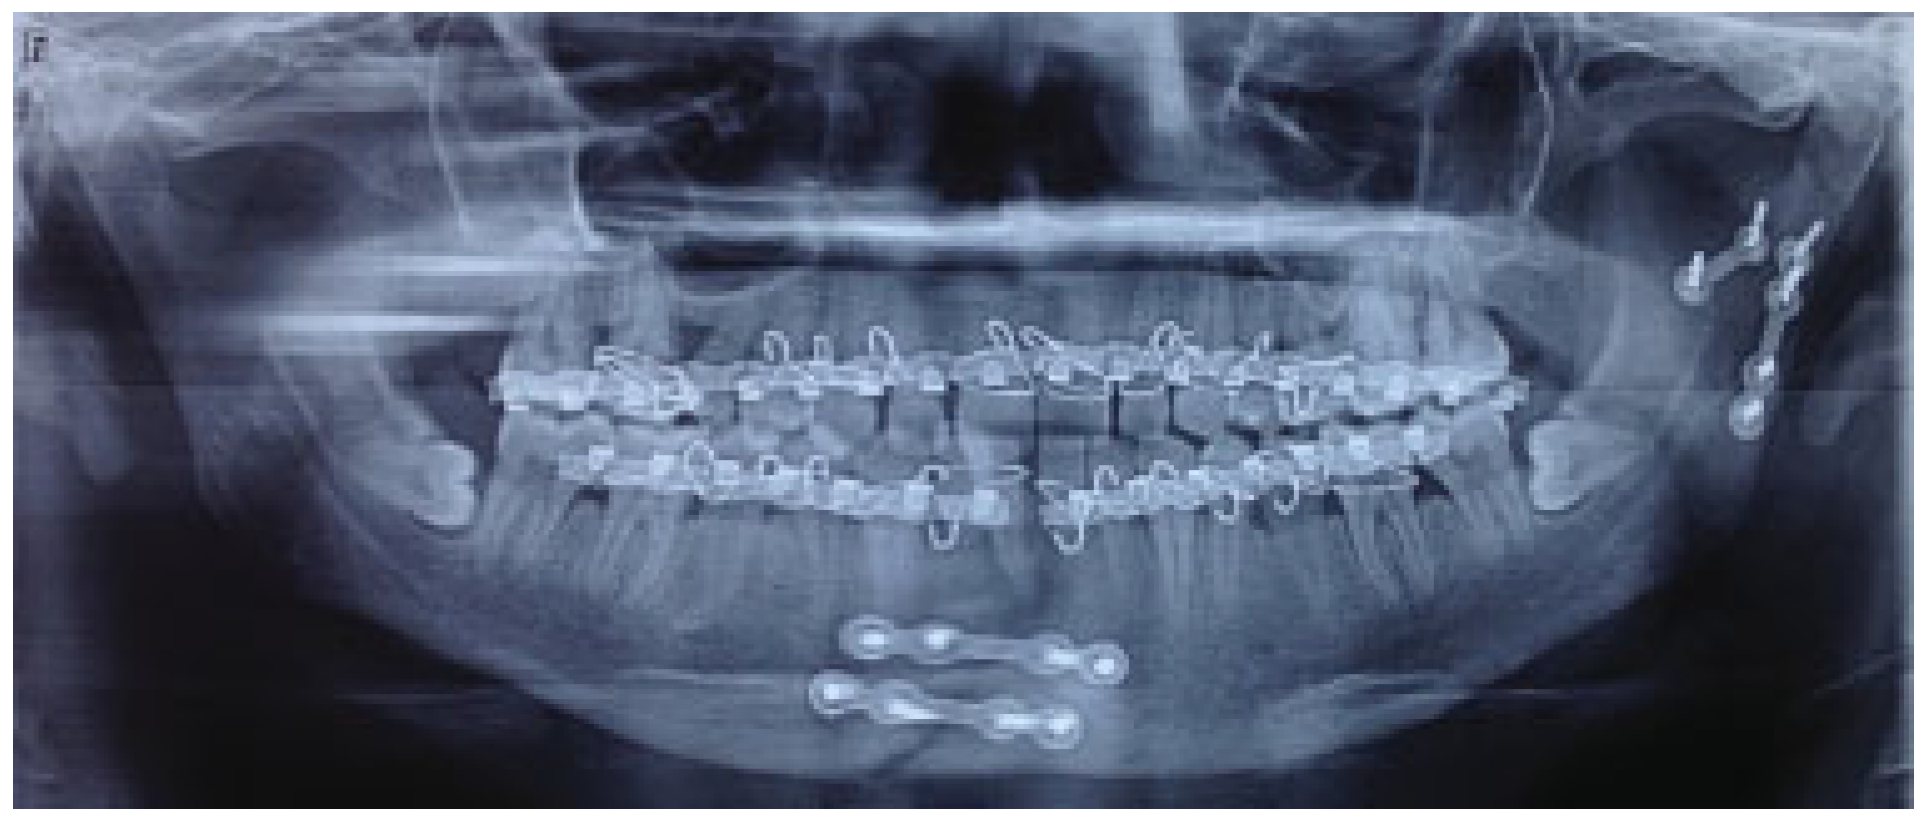

The mean for ramal height shortening was found to be 11.9 (0.99) preoperatively and 11.6 (1.57) postoperatively in Group A. It was compared using paired t-test and this difference was found not to be statistically significant (p = 0.34; Figure 1 and Figure 2). The mean for ramal height shortening was found to be 12.5 (0.84) preoperatively and (0.87) postoperatively in Group B. It was compared using paired t-test and this difference was found to be statistically significant (p < 0.05; Figure 3 and Figure 4).

Figure 4.

Group B: Postoperative orthopantomography.

The mean for fracture displacement was found to be 29.9 (4.67) preoperatively and 28.2 (5.67) postoperatively in Group A. It was compared using paired t-test and this difference was found not to be statistically significant (p < 0.34). The mean for fracture displacement was found to be 30.9 (3.14) preoperatively and 1.8 (1.47) postoperatively in Group B. It was compared using paired t-test and this difference was found to be statistically significant (p < 0.05; Table 2).